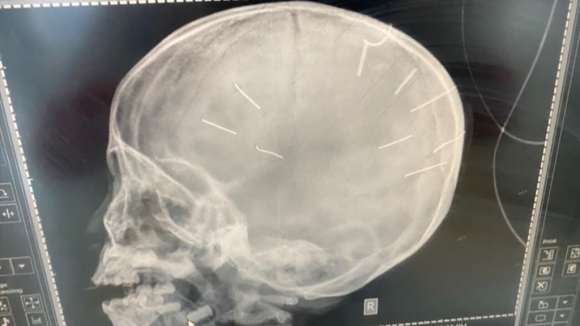

Hình ảnh chụp hộp sọ bé Đ.N.A - BVCC |

Theo lãnh đạo Bệnh viện đa khoa H.Thạch Thất, sau khi Bệnh viện Xanh Pôn tiến hành chụp cắt lớp thì có 9 chiếc đinh găm trong não bệnh nhi, tình trạng bệnh nhi nặng, khả năng tử vong rất cao.